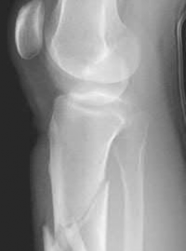

Figure A is an AP radiograph of a posterior knee dislocation. Figure B is a lateral showing the same injury.